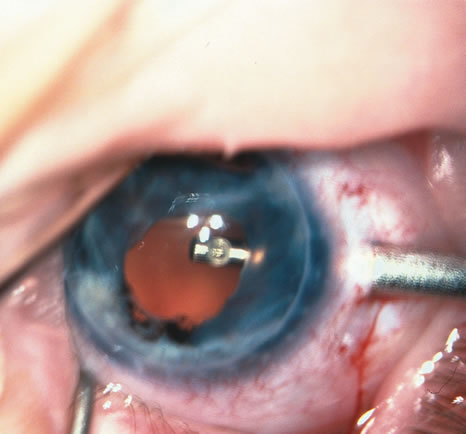

When the vitreous suction-cutting devices became available, they were quickly employed to remove cataracts in children. In addition to providing control of aspiration pressure and control of the flow of irrigation solutions, they also added the ability to remove some or all of the posterior lens capsule, even when the capsule had a thick fibrovascular stalk associated with persistent hyperplastic primary vitreous (PHPV) or a thick capsular plaque (Fig. 2). These fine-tip suction-cutting instruments provided sufficient control of the anterior chamber depth, thus permitting the surgeon to precisely open the posterior capsule and, if necessary, safely remove vitreous from the anterior chamber. Keech and co-workers,12 in a contemporaneous surgical series, showed that having the ability to remove the posterior lens capsule and perform an anterior vitrectomy reduced the need for secondary procedures from 75%, if the capsule was left intact, to 11% after capsulectomy and anterior vitrectomy. They found that when a large section of the posterior lens capsule was removed, it provided a lasting optical opening and reduced the requirement for additional surgery.